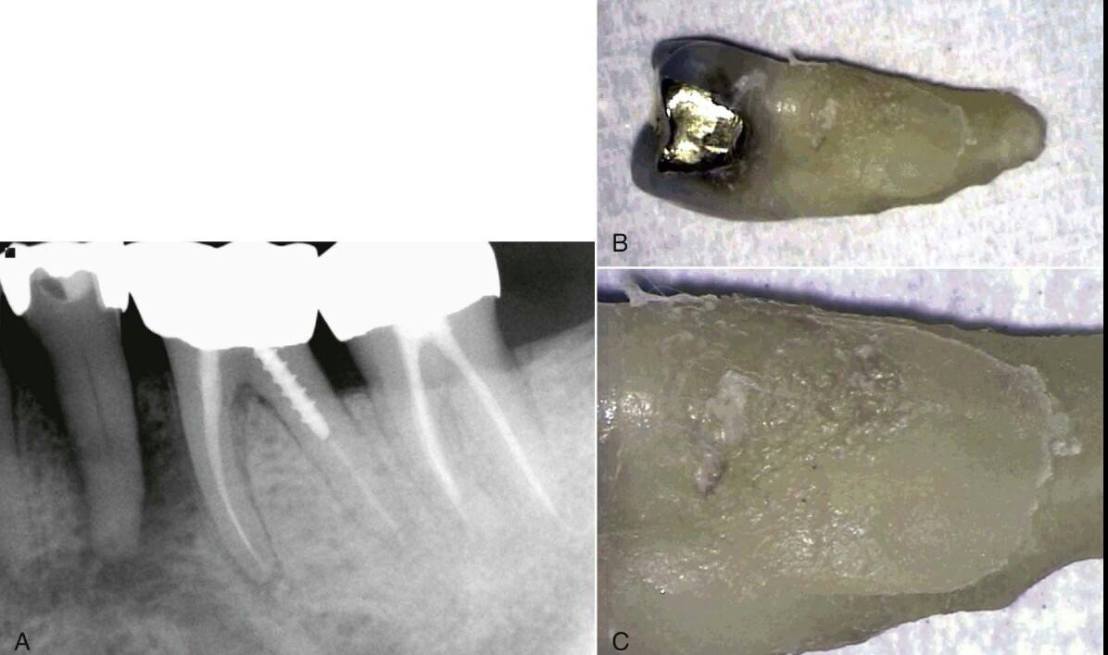

อีกกรณีที่ต้องคำนึงถึง คือ ทดสอบได้ว่าฟันมี pulp necrosis โดยไม่พบข้อบ่งชี้เฉพาะ ไม่พบ deep caries หรือ มี filling ที่ตื้นมาก แต่ฟันกลับตาย (ในรูป ด้าน Distal ของ root พบ Oblique vertical root fracture)

อีก case สังเกต filling ตื้นมาก แต่ฟัน non-vital และพบรอย crack ทางด้าน distal เมื่อถอนออกมาแล้ว